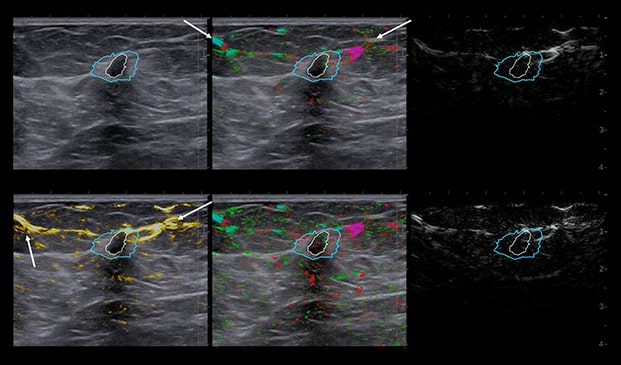

Case Example 2:

48-year-old female, presented with an abnormal mammogram/tomo. 1.9 cm mass seen on ultrasound, negative doppler.

Case Example 2: Observations

Deoxygenated hemoglobin internal to the mass is represented by intense disorganized or polymorphic pink colorization seen on the 6-up image.

These are typical malignant characteristics on OA which are represented on the combined map (upper middle), total hemoglobin (lower left) and relative map (lower middle).

Invasive Ductal Carcinoma Grade III

- ER-

- HER2-

- PR-

- Ki67=80%

The Mass was up-classified to BI-RADS 4C. Biopsy confirmed triple negative cancer. TNC masses typically present with intense deoxygenated mainly internal vessels. Masses with high Ki67 tend to have a lot of internal vessels mainly in the internal and boundary zones, unless there is necrosis.